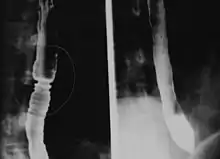

The barium swallow of the esophagus on the left side shows multiple rings associated with eosinophilic esophagitis.

Radiologically, the term "ringed esophagus" has been used for the appearance of eosinophilic esophagitis on barium swallow studies to contrast with the appearance of transient transverse folds sometimes seen with esophageal reflux (termed "feline esophagus").[12]